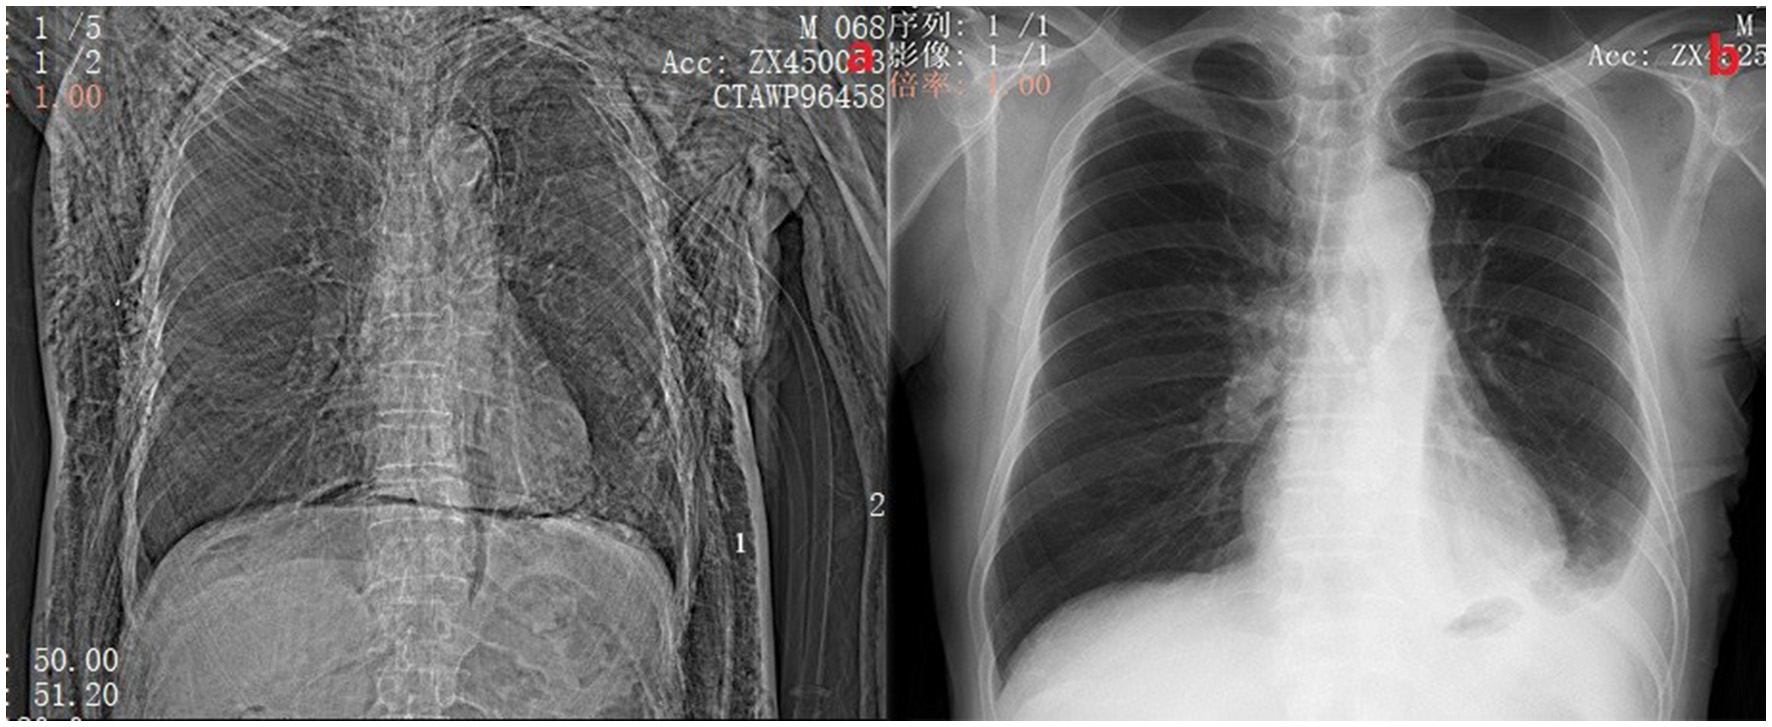

Figure 2

(A) Shows a patient with postoperative pneumothorax and subcutaneous emphysema with 2 chest tubes inserted. The side marked with 1 is the chest tube placed during surgery, and the side marked with 2 is the chest tube placed at the bedside. (B) Shows a chest X-ray of the same patient 2 weeks after discharge.

All patients underwent uniportal VATS procedure and were performed by the same surgical team. All patients received standardized pulmonary resection and mediastinal lymphadenectomy according to the Chinese Medical Association guidelines for the clinical diagnosis and treatment of lung cancer (edition 2018). The incision hole was located at the anterior axillary line of the 4th or 5th interspace for pulmonary resection (including lobectomy and Sub-lobar resection) and lymphadenectomy with a length of 3–4 cm. Generally, the 4th interspace for right lobes and the 5th interspace for left lobes. At the end of surgery, the conventional chest tube (24 Fr, 8.00 mm in diameter) was used. The chest tube was inserted from the incision straight to the top of the chest through the anterior mediastinum pathway, which was connected to water-seal bottles without negative pressure. After the operations, we collected the postoperative thoracic drainage volume, the average VAS pain scores in incisions, average hospital stay time, chest tube removal time during the perioperative period, levels of serum CRP and pulmonary complications during hospitalization. If the chest X-ray or CT shows that the residual lung re-expansion and without obvious inflammation (Reference the levels of serum C-reactive protein (CRP) and bodies' temperature), and the patient with no obvious complaints of discomfort, then the patient was acceptable criteria for discharge (Figure 2b). 2 weeks after discharge, the incision sutures were removed and chest X-rays were reviewed. A follow-up chest CT scan was also performed 1 month after discharge to ensure the patient's recovery.